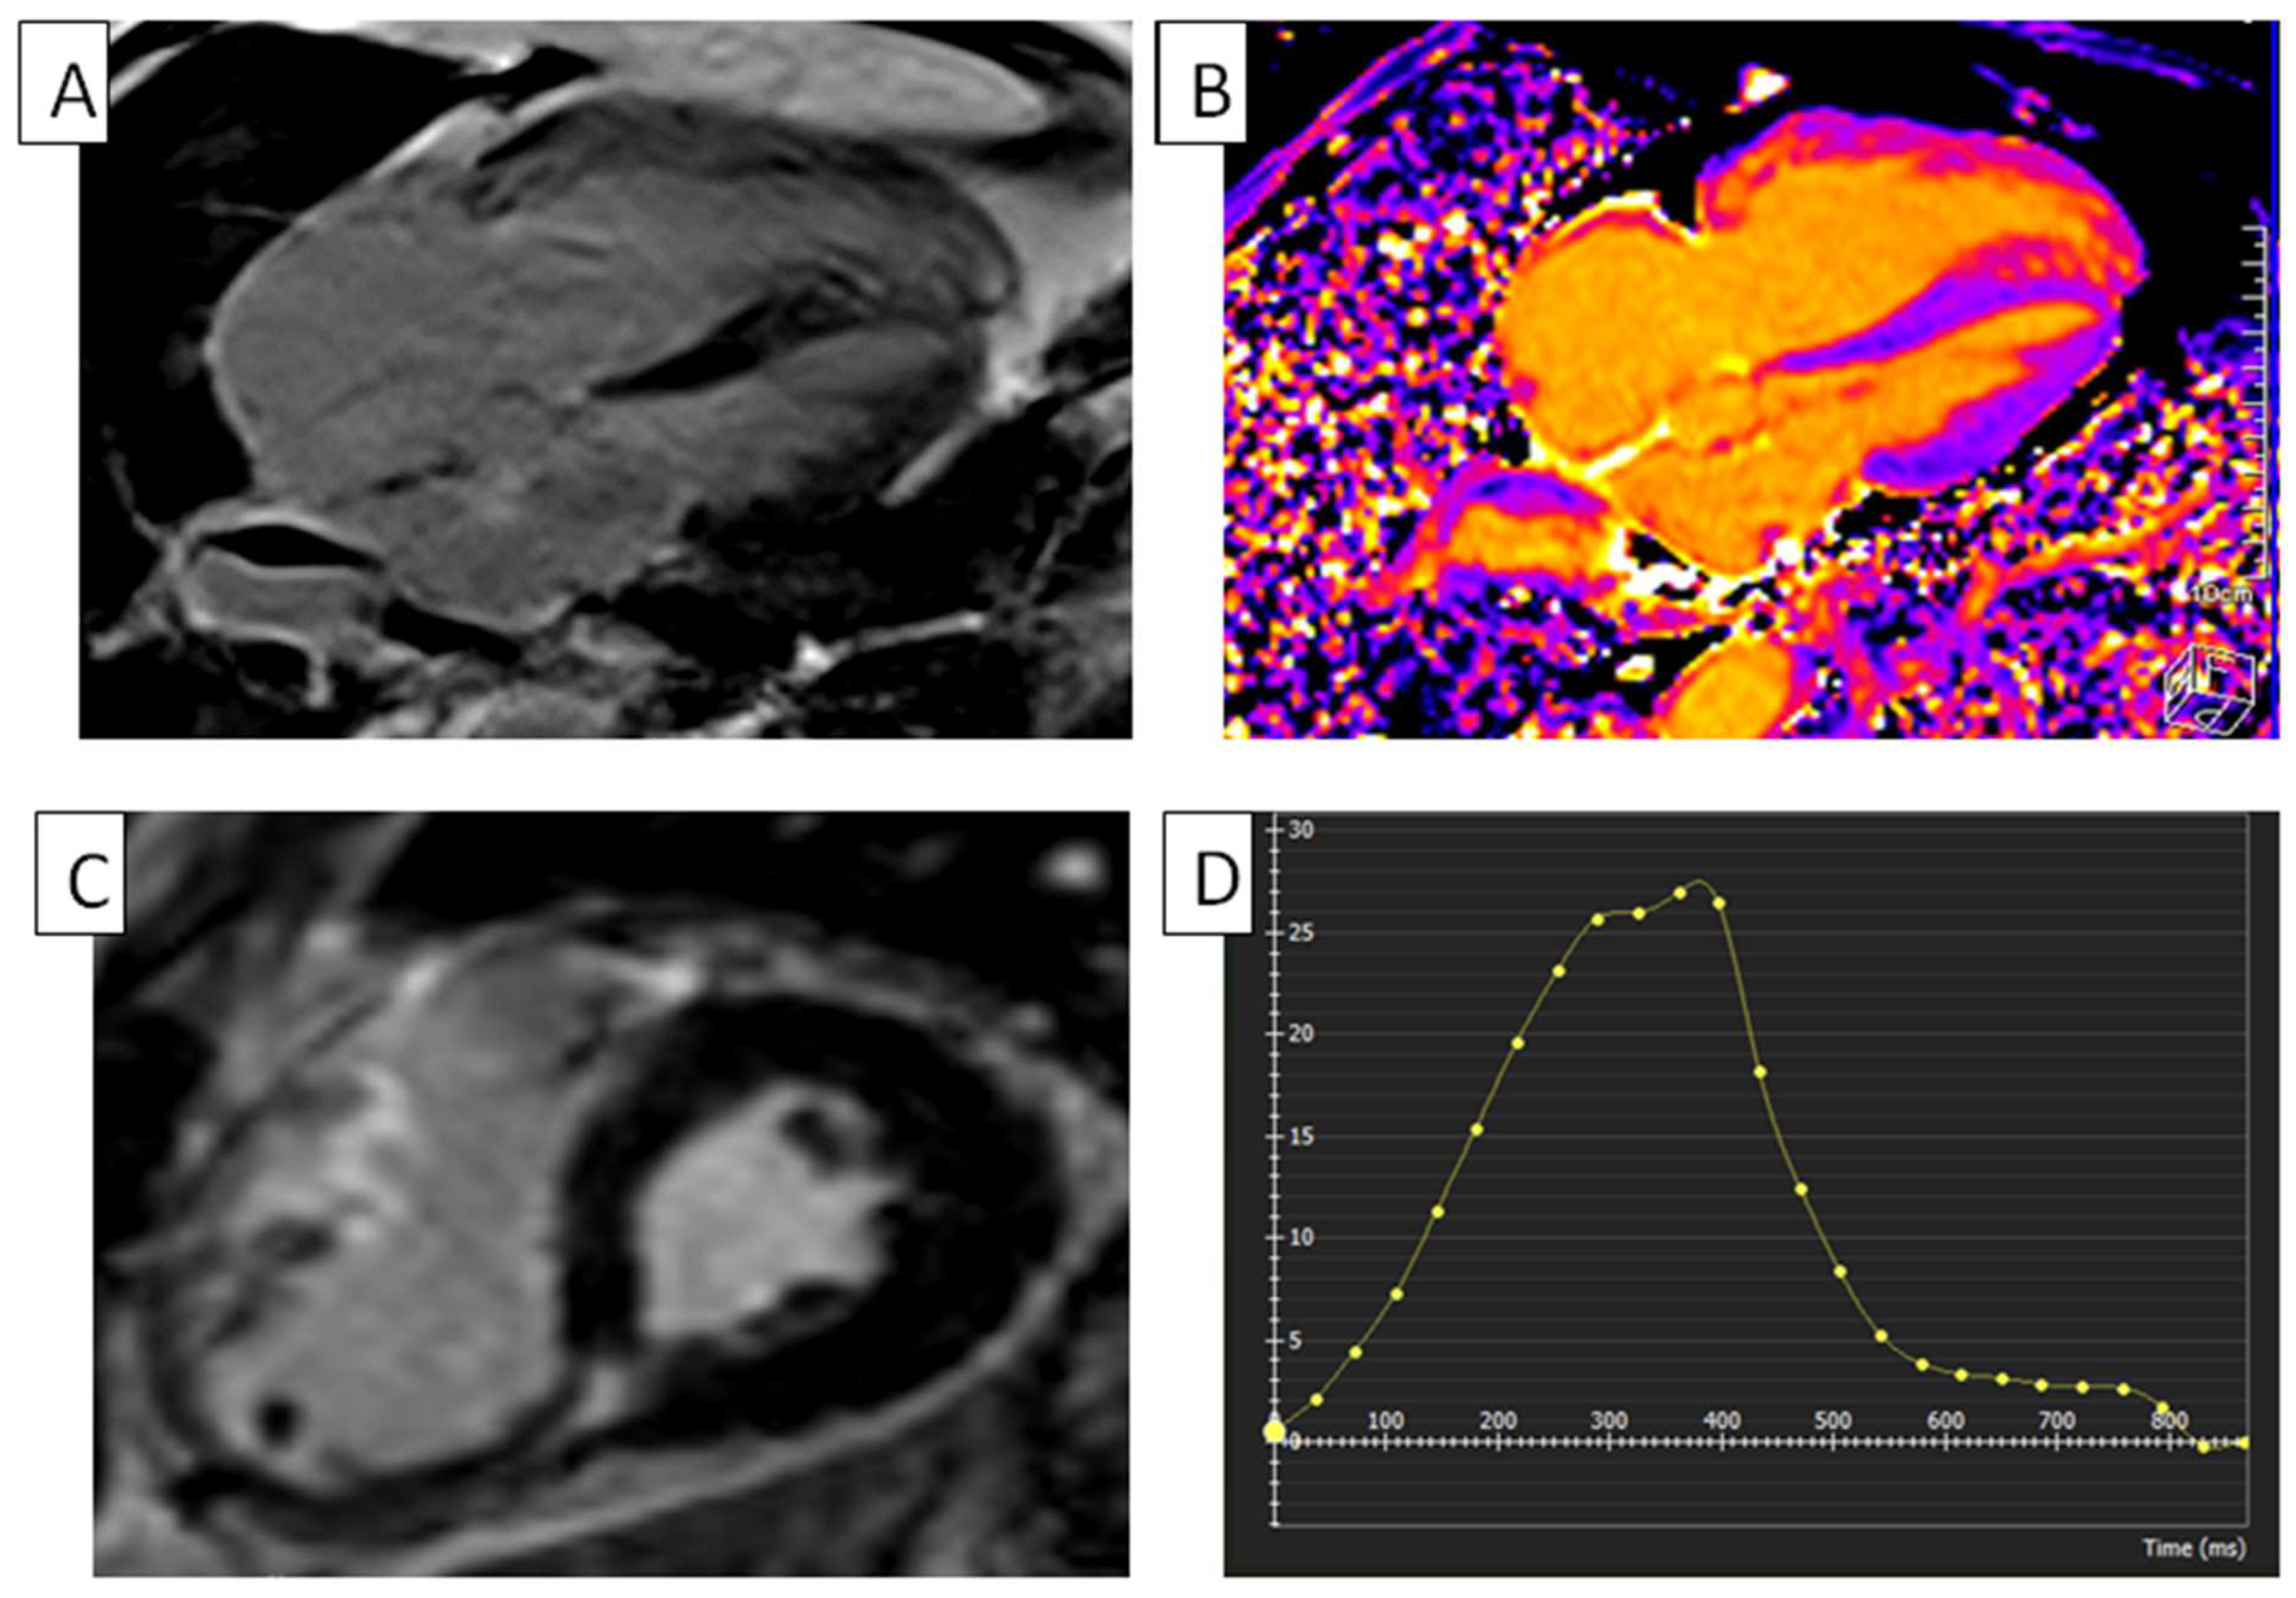

5.5. Hypertrophic Cardiomyopathy

5.6. Amyloidosis

- Eckstein, J.; Körperich, H.; Weise Valdés, E.; Sciacca, V.; Paluszkiewicz, L.; Burchert, W.; Farr, M.; Sommer, P.; Sohns, C.; Piran, M. CMR-based right ventricular strain analysis in cardiac amyloidosis and its potential as a supportive diagnostic feature. Int. J. Cardiol. Heart Vasc. 2023, 44, 101167. [Google Scholar] [CrossRef] [PubMed]

- Qian, Y.; Zhao, X.; Chen, B.-H.; An, D.-A.; Wu, R.; Shi, R.-Y.; Zhang, C.; Ma, X.; Zhou, Y.; Zhao, L.; et al. Right ventricular global strain in patients with hypertrophic cardiomyopathy with and without right ventricular hypertrophy. Eur. J. Radiol. 2023, 169, 111148. [Google Scholar] [CrossRef] [PubMed]

- Mahmod, M.; Raman, B.; Chan, K.; Sivalokanathan, S.; Smillie, R.W.; Samat, A.H.A.; Ariga, R.; Dass, S.; Ormondroyd, E.; Watkins, H.; et al. Right ventricular function declines prior to left ventricular ejection fraction in hypertrophic cardiomyopathy. J. Cardiovasc. Magn. Reson. 2022, 24, 36. [Google Scholar] [CrossRef] [PubMed]

- Yang, F.; Wang, J.; Li, Y.; Li, W.; Xu, Y.; Wan, K.; Sun, J.; Han, Y.; Chen, Y. The prognostic value of biventricular long axis strain using standard cardiovascular magnetic resonance imaging in patients with hypertrophic cardiomyopathy. Int. J. Cardiol. 2019, 294, 43–49. [Google Scholar] [CrossRef] [PubMed]

- Balasubramanian, S.; Faisaluddin, M.; Gaznabi, S.; Nso, N. Prognostic Value of Right Ventricular Strain on CMR in Patients with Cardiac Amyloidosis: A Meta-analysis Study. J. Cardiovasc. Magn. Reson. 2024, 26, 100693. [Google Scholar] [CrossRef]

- Liu, H.; Fu, H.; Guo, Y.-K.; Yang, Z.-G.; Xu, H.-Y.; Shuai, X.; Xu, R.; Li, Z.-L.; Xia, C.-C.; He, Y.; et al. The prognostic value of right ventricular deformation derived from cardiac magnetic resonance tissue tracking for all-cause mortality in light-chain amyloidosis patients. Cardiovasc. Diagn. Ther. 2020, 10, 161–172. [Google Scholar] [CrossRef]